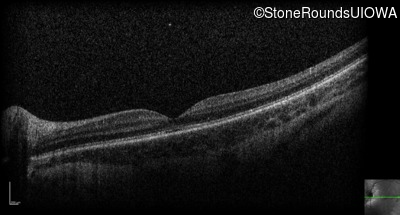

Optical Coherence Tomography - Right - 10/125 +2

Exemplar / OCT Stack

OCT Stack

Optical Coherence Tomography - Left - 10/160